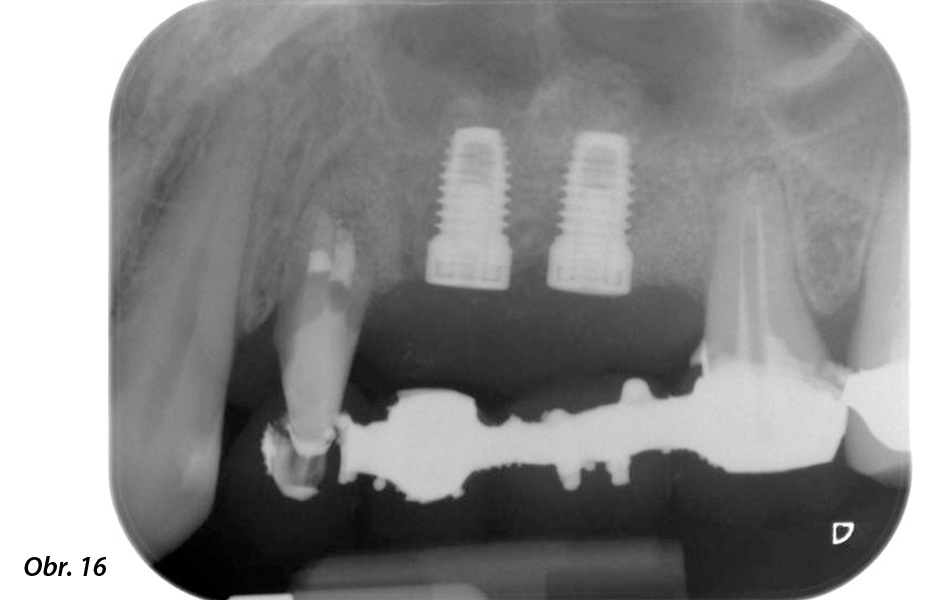

Nakonec, po provedení periosteálního řezu, bylo místo spolu s koronálně posunutým lalokem pasivně sešito vstřebatelným šicím materiálem 5-0 (obr. 15). Pooperační RTG snímek prokázal, že jsou oba implantáty ve správné vertikální pozici (obr. 16).

Pooperační RTG snímek zachycující zavedené implantáty s kostní náhradou transplantovanou kolem apexů při vnitřním sinus liftu – kolem kořenů zubu 24 je vidět i materiál z GTR procedury.